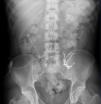

Ours was a 47 year-old patient with chronic renal failure from interstitial nephropathy secondary to reflux, who had been on haemodialysis since 1990. He underwent his first kidney transplant in 1991, which was then removed due to chronic dysfunction, and underwent a second transplant in 1999, which was again lost to the same reasons. He returned to haemodialysis in 2010. Due to intolerance to the second kidney, the patient underwent graft embolisation. He was receiving lanthanum carbonate at 750mg/8 hours due to secondary hyperparathyroidism and hyperphosphataemia. Due to several failed vascular accesses, it was suggested that the patient be transferred to peritoneal dialysis, and a straight, double-cuff Tenckhoff catheter was implanted. During training, we detected catheter malfunction with incomplete drainage, so we performed abdominal x-rays (Figure 1) and peritoneography (Figure 2). In addition to the remnants of the radio-opaque material from the graft embolisation, we observed a large quantity of faecal matter throughout the large intestine, with radiolucent images indicating the presence of lanthanum carbonate. The peritoneal catheter was poorly positioned towards the hepatic flexure of the colon, and the peritoneography dye was completely restricted between the transverse colon and the lower edge of the liver, which was clearly outlined, without disseminating into the rest of the abdominal cavity. Suspension of the lanthanum and intensive laxative treatment progressively resolved the constipation and dye restriction, although it did not resolve the poor positioning of the catheter, which had to be relocated.

Figure 2. Peritoneography